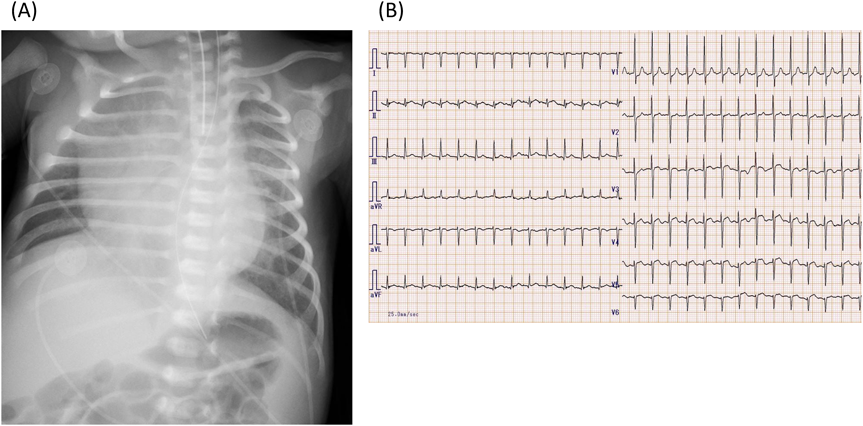

Blood tests on day 9 demonstrated elevated cardiac enzymes with CK 569U/L, Troponin I 4813.6 pg/mL as well as BNP 4131. 4 pg/mL and IgM 204 mg/dL (Table 1). Chest X-ray (Fig. 1) showed cardiomegaly with a cardiothoracic ratio of 67%. Twelve-lead electrocardiography (Fig. 1) showed ST-T changes in the precordial leads. Echocardiography revealed left ventricular dilatation with a left ventricular end-diastolic diameter (LVDD) of 26.3 mm, and left ventricular ejection fraction (LVEF) was markedly reduced to 33%. There was moderate mitral regurgitation and moderate tricuspid regurgitation. The systolic displacement of the tricuspid annulus (TAPSE) was decreased to 3 mm, and pulmonary hypertension was present based on increased tricuspid regurgitation pressure gradient (TRPG) of 59 mmHg. There were no pulmonary artery stenosis or pulmonary vein stenosis. A small pericardial effusion was noted.

Fig. 1 Chest X-ray (A) and Electrocardiography (B) on admission